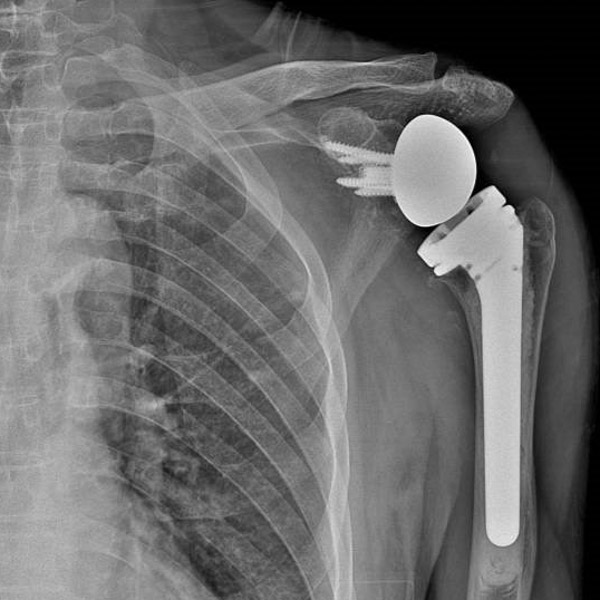

▲術(shù)前術(shù)后對比

幾天后,江爺爺被推進了手術(shù)室,由于進行了多次預(yù)演,手術(shù)過程非常順利,術(shù)中處理關(guān)節(jié)面、置入假體,關(guān)節(jié)穩(wěn)定不易脫位,透視見假體位置良好,修補重建肩袖和關(guān)節(jié)囊……一個多小時以后,手術(shù)圓滿結(jié)束。

目前,江爺爺已經(jīng)成功出院進入術(shù)后康復(fù)階段,疼痛感大大減輕,肩關(guān)節(jié)也漸漸能夠活動了,相信通過一段時間的康復(fù)治療,他便能徹底告別病痛,回歸正常生活。